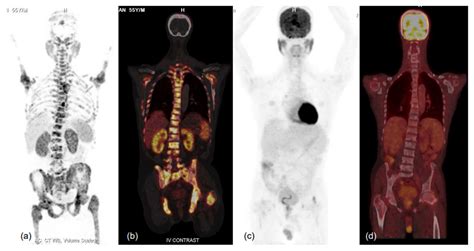

At its core, a Pet Ct scan is designed to provide both functional and structural information. While a traditional CT scan uses X-rays to create detailed pictures of organs and tissues, a PET scan uses a small amount of radioactive tracer to highlight areas of high metabolic activity. This is particularly crucial in oncology, as cancer cells often exhibit higher metabolic rates than healthy cells.

When these two technologies are combined into a single Pet Ct machine, the results are fused together. This allows doctors to pinpoint the exact location of a biological abnormality and observe its physical size and shape simultaneously. The fusion of this data is what makes it a gold standard in modern diagnostics.

• Oncology: Used to diagnose, stage, and monitor the effectiveness of cancer treatments.